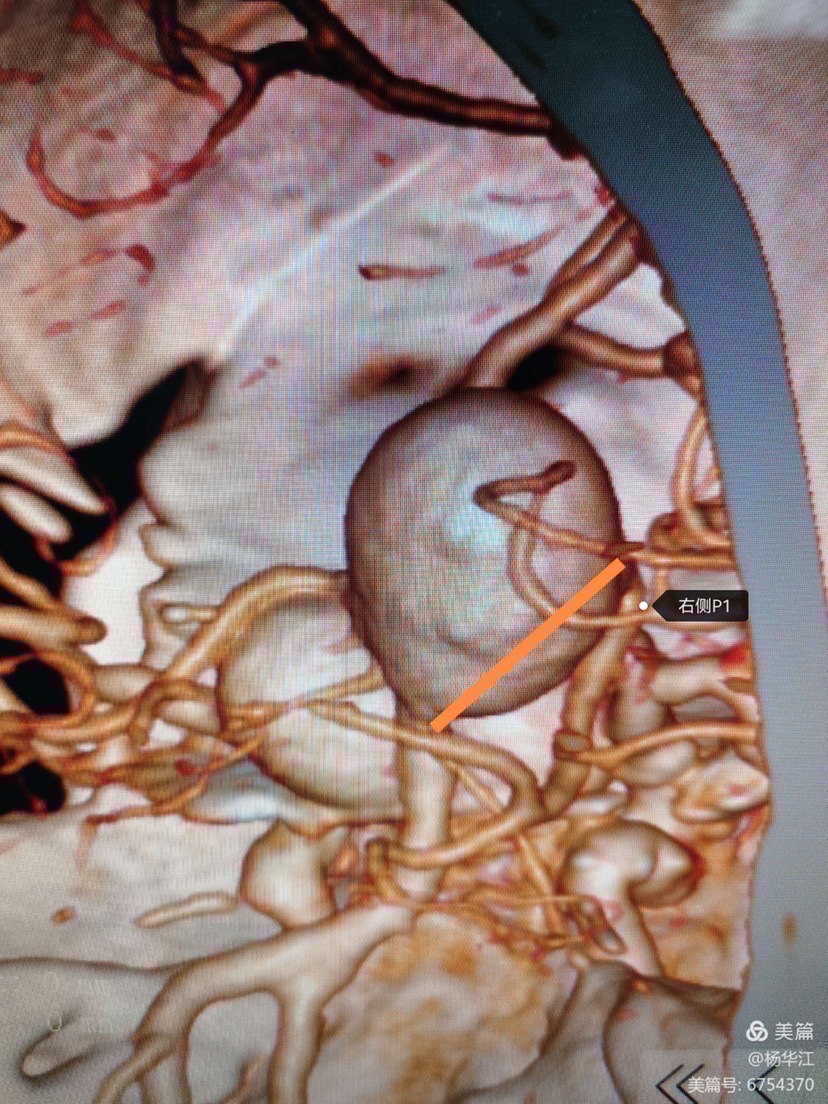

CTA及DSA显示:颈内动脉床突上段巨大动脉瘤(最大径25.6mm);基底动脉尖大动脉瘤(最大径20.3mm),瘤颈宽11mm,累及双侧大脑后动脉、小脑上动脉,右侧大脑后动脉自瘤体侧后方发出。

这是我们用了10年之久西门子机器做出的3D后处理影像,还行吧,尽管稍有些失真。